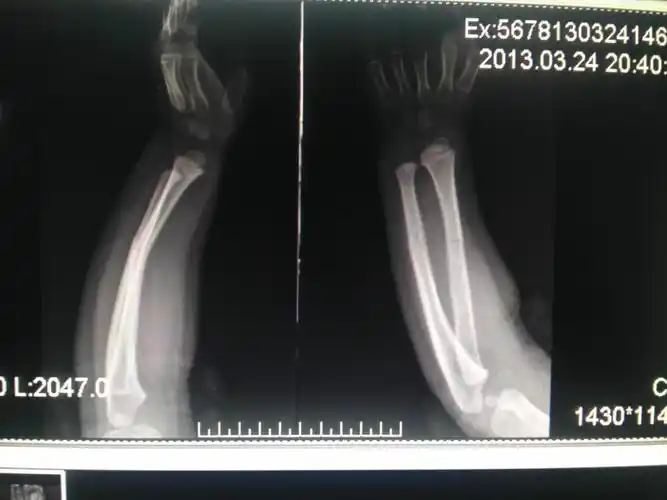

原创原创儿童尺桡骨下端骨折治疗方法

左尺桡骨折青枝骨折

儿童桡骨远端骨折手法复位一例

左侧腕部骨折

儿童桡骨下段青枝骨折手法治疗